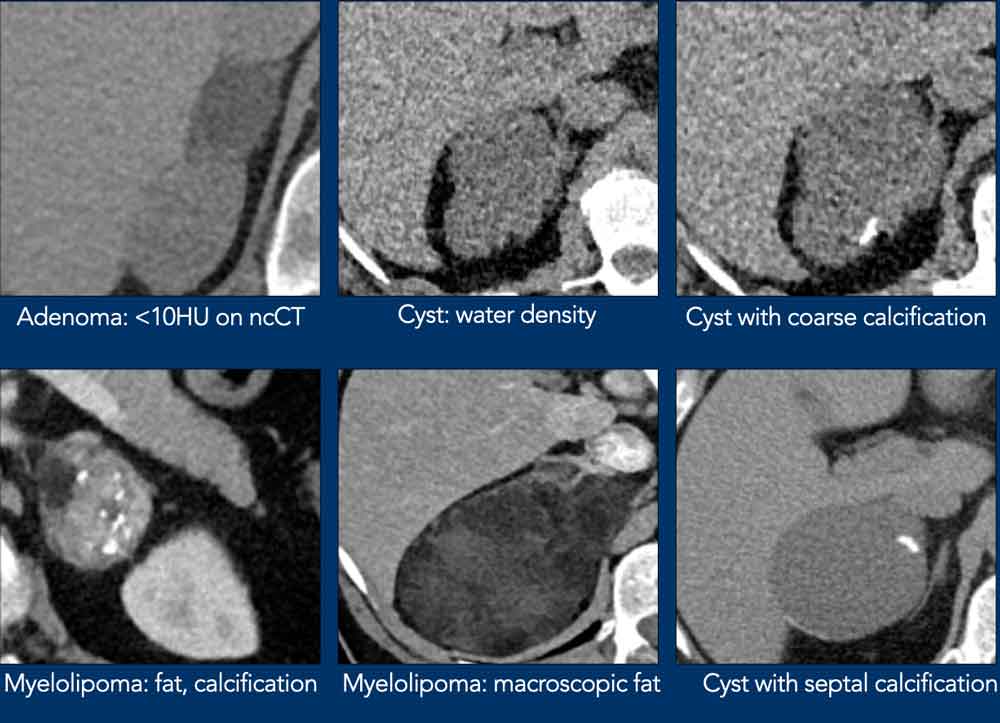

Many adrenal lesions can be categorized as typically benign and need no follow up:

• Lipid-rich adenoma (density <10HU)

• Myelolipoma (macroscopic fat)

• Cyst (low density, no enhancement)

Lipid-Rich Adenoma

Approximately 70% of adrenal adenomas are lipid-rich, characterized by high intracellular fat content and consequently demonstrating low attenuation on unenhanced CT.

Myelolipomas

Adrenal myelolipomas are benign, uncommon adrenal tumors (prevalence: 0.08–0.2%), composed of variable proportions of hematopoietic bone marrow elements and mature adipose tissue.

These lesions are typically asymptomatic, although large myelolipomas may become symptomatic due to mass effect or spontaneous hemorrhage.

The presence of macroscopic fat enables straightforward identification on CT or MRI.

On nonenhanced CT, attenuation values are characteristically below 0 HU.

Calcifications are observed in approximately 24% of cases.

Cysts

Adrenal cysts are well-defined, round, homogenous, low-attenuation (<20 HU) lesions.

They may show calcifications or septations.

Lesions with benign calcifications

Coarse rounded, peripheral or septal calcifications are typically benign and may be seen in: